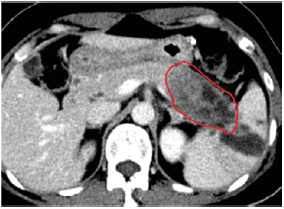

CT와 MRI는 췌장암 진단에 있어 매우 중요한 영상 진단법입니다. 특히 CT는 췌장 내 종양의 위치와 크기를 명확하게 파악할 수 있어 초기 진단과 치료 계획에 도움을 줍니다. - 내시경 초음파(EUS)